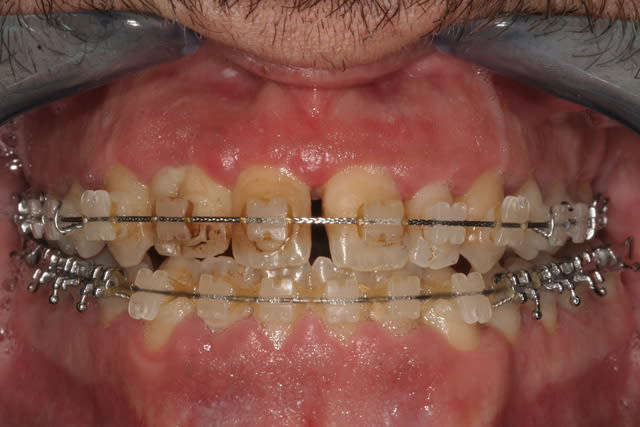

je vois un patient hier en 1ere consultation car son ortho (que je ne connais pas) l'envoie pour faire des facettes car le patient à une demande esthétique importante...

- Quid de la 22... Comment feriez vous ?

L'ortho travaille sur ce qui ressemble à une parodontite non stabilisée, ne s'est pas occupé en amont de la dent géminée et n'a pas rétabli une occlusion correcte. Cela, cumulé aux dastèmes, amène à un haut risque que tout bouge très rapidement une fois débagué. Réfléchis bien si tu as envie de prendre la suite ou non.

Ce patient aurait peut-être eu besoin d'un traitement orthochirurgical pour obtenir un résultat parfait d'un point de vue occlusal (enfin du peu qu'on en voit je suppose). L'ortho l'a-t-il proposé ? Le patient a-t-il refusé ? De même, le patient a-t-il bien fait ce que l'ortho lui a demandé (port d'éventuels auxiliaires par exemple) ? Impossible à dire.

Tout ce qu'on voit c'est que l'hygiène est mauvaise, ce qui laisse penser que le patient n'est peut-être pas très sérieux...

Reste qu'il est étonnant que l'asymétrie 12/22 n'ait pas été gérée en amont par l'ODF, car même avec des facettes jamais le résultat ne pourra être satisfait. Si des facettes (ou compos) sont prévus pour gérer l'assymétrie 12/22 l'ortho doit en amont positionner les racines de manière idéale en contrôlant l'emplacement et la taille des diastèmes.

C'est pas pour défendre l'ortho qui prend en charge ce patient mais je pense sur le plan occlusal il pourra pas faire grand chose a part améliorer l'occlusion latérale au niveau du secteur premolaire et molaire parcequ'apparemment c'est une DDD par excès mandibulaire au niveau des 6 dents antérieures qui se traite généralement par stripping des incisives et canines mandibulaires

+ TIM de classe III sinon l'augmentation des largeurs des dents anterieures maxillaires (incisives et canines)par des rajouts de composite ou carrément par un bridge de 6 elements qui en plus sera un bon moyen de contention definitive, maintenant je sais pas si des facettes en ceramiques feraient l'affaire.